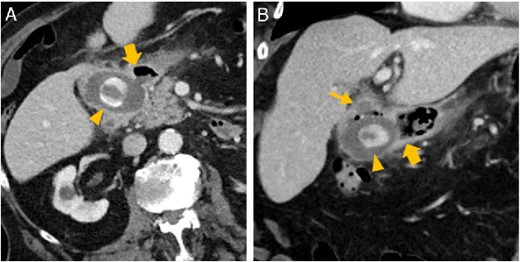

Abdominal CT in axial (A) and oblique paracoronal reconstruction (B); gallstone in the duodenal bulb (arrowhead

), pylorus (thick arrow

), chronically inflamed, and collapsed gall bladder with fistula to the duodenum (thin arrow

); image courtesy of Gerald Wolf, State Hospital Western Styria, Austria.